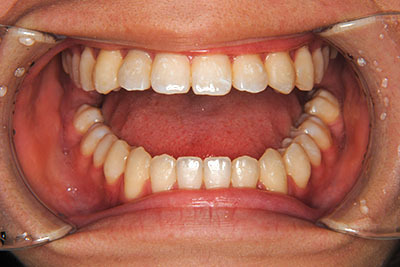

歯が乳歯から永久歯に生え変わった小学生高学年や、中高生でも矯正治療に手遅れということは全くありません。

成長中の顎の骨を矯正できたり、この時期の矯正はおとなになってから矯正治療を始めるよりも短期間で済むことがほとんどです。当院だとおおよそ1年で動的治療(マルチブラケット装置をつける期間)が終わることが多いです。